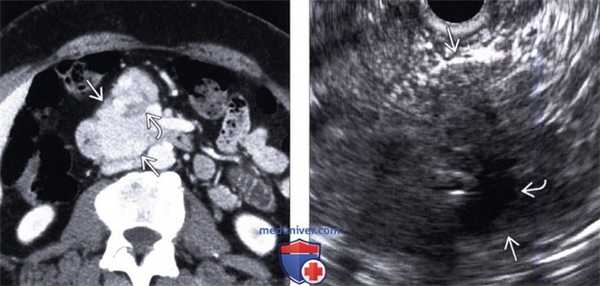

(Левый) При КТ с контрастным усилением на аксиальной томограмме в головке поджелудочной железы визуализируется крупное гиперваскулярное объемное образование, содержащее мелкий очаг слабого коэффициента ослабления - зону централь ного некроза.

(Правый) При эндоскопическом УЗИ на соответствующем УЗ срезе определяется дольчатое четко отграниченное изоэхогенное солидное объемное образование, содержащее гипоэхогенный очаг кистозных изменений.